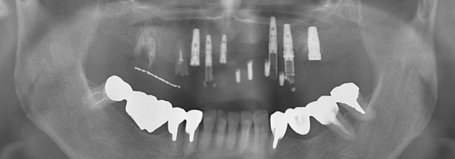

インプラントの治療例3

入れ歯が安定しないということで来院された患者様です。

入れ歯を支えていた両側の一番外の歯が黒くなっているのが分かりますか?

このように、入れ歯はそれを支える天然歯に大きな悪影響を及ぼします。

結果として、この歯は抜歯となり、インプラントを行いました。

治療前

治療後